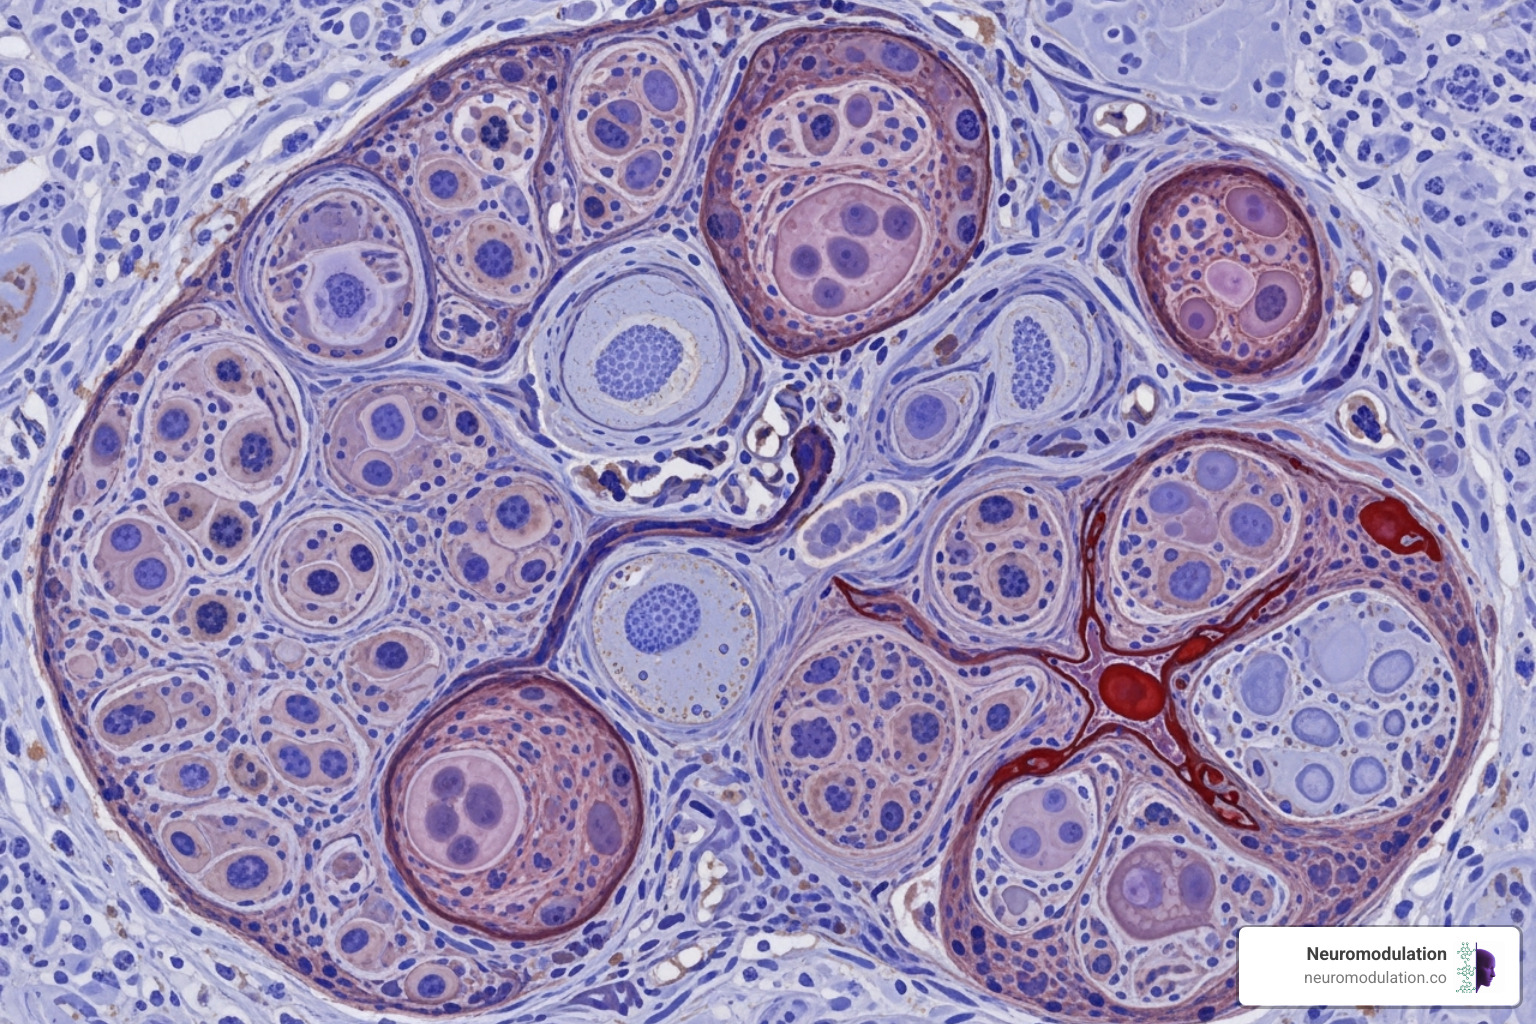

Nanoparticles: The Vehicles for Targeted Therapy

Nanoparticles are the microscopic delivery vehicles of targeted therapy. Measuring just a few to several hundred nanometers—thousands of times smaller than a human hair—these carriers protect drugs, steer biological barriers, and release their payload at the right time and place.

The world of nanocarriers is diverse, with each type offering unique properties. Some of the most common include:

- Liposomes: Tiny bubbles made from the same materials as cell membranes, capable of carrying various drug types.

- Polymeric micelles: Self-assembling particles that create pockets for drugs that don’t dissolve well in water.

- Dendrimers: Tree-like structures with many branches for attaching drugs and targeting molecules.

- Inorganic nanoparticles: Made from materials like gold or silica, offering excellent biocompatibility and easy customization.

- Hydrogels: Polymer networks that absorb water and are ideal for sustained, localized drug release.